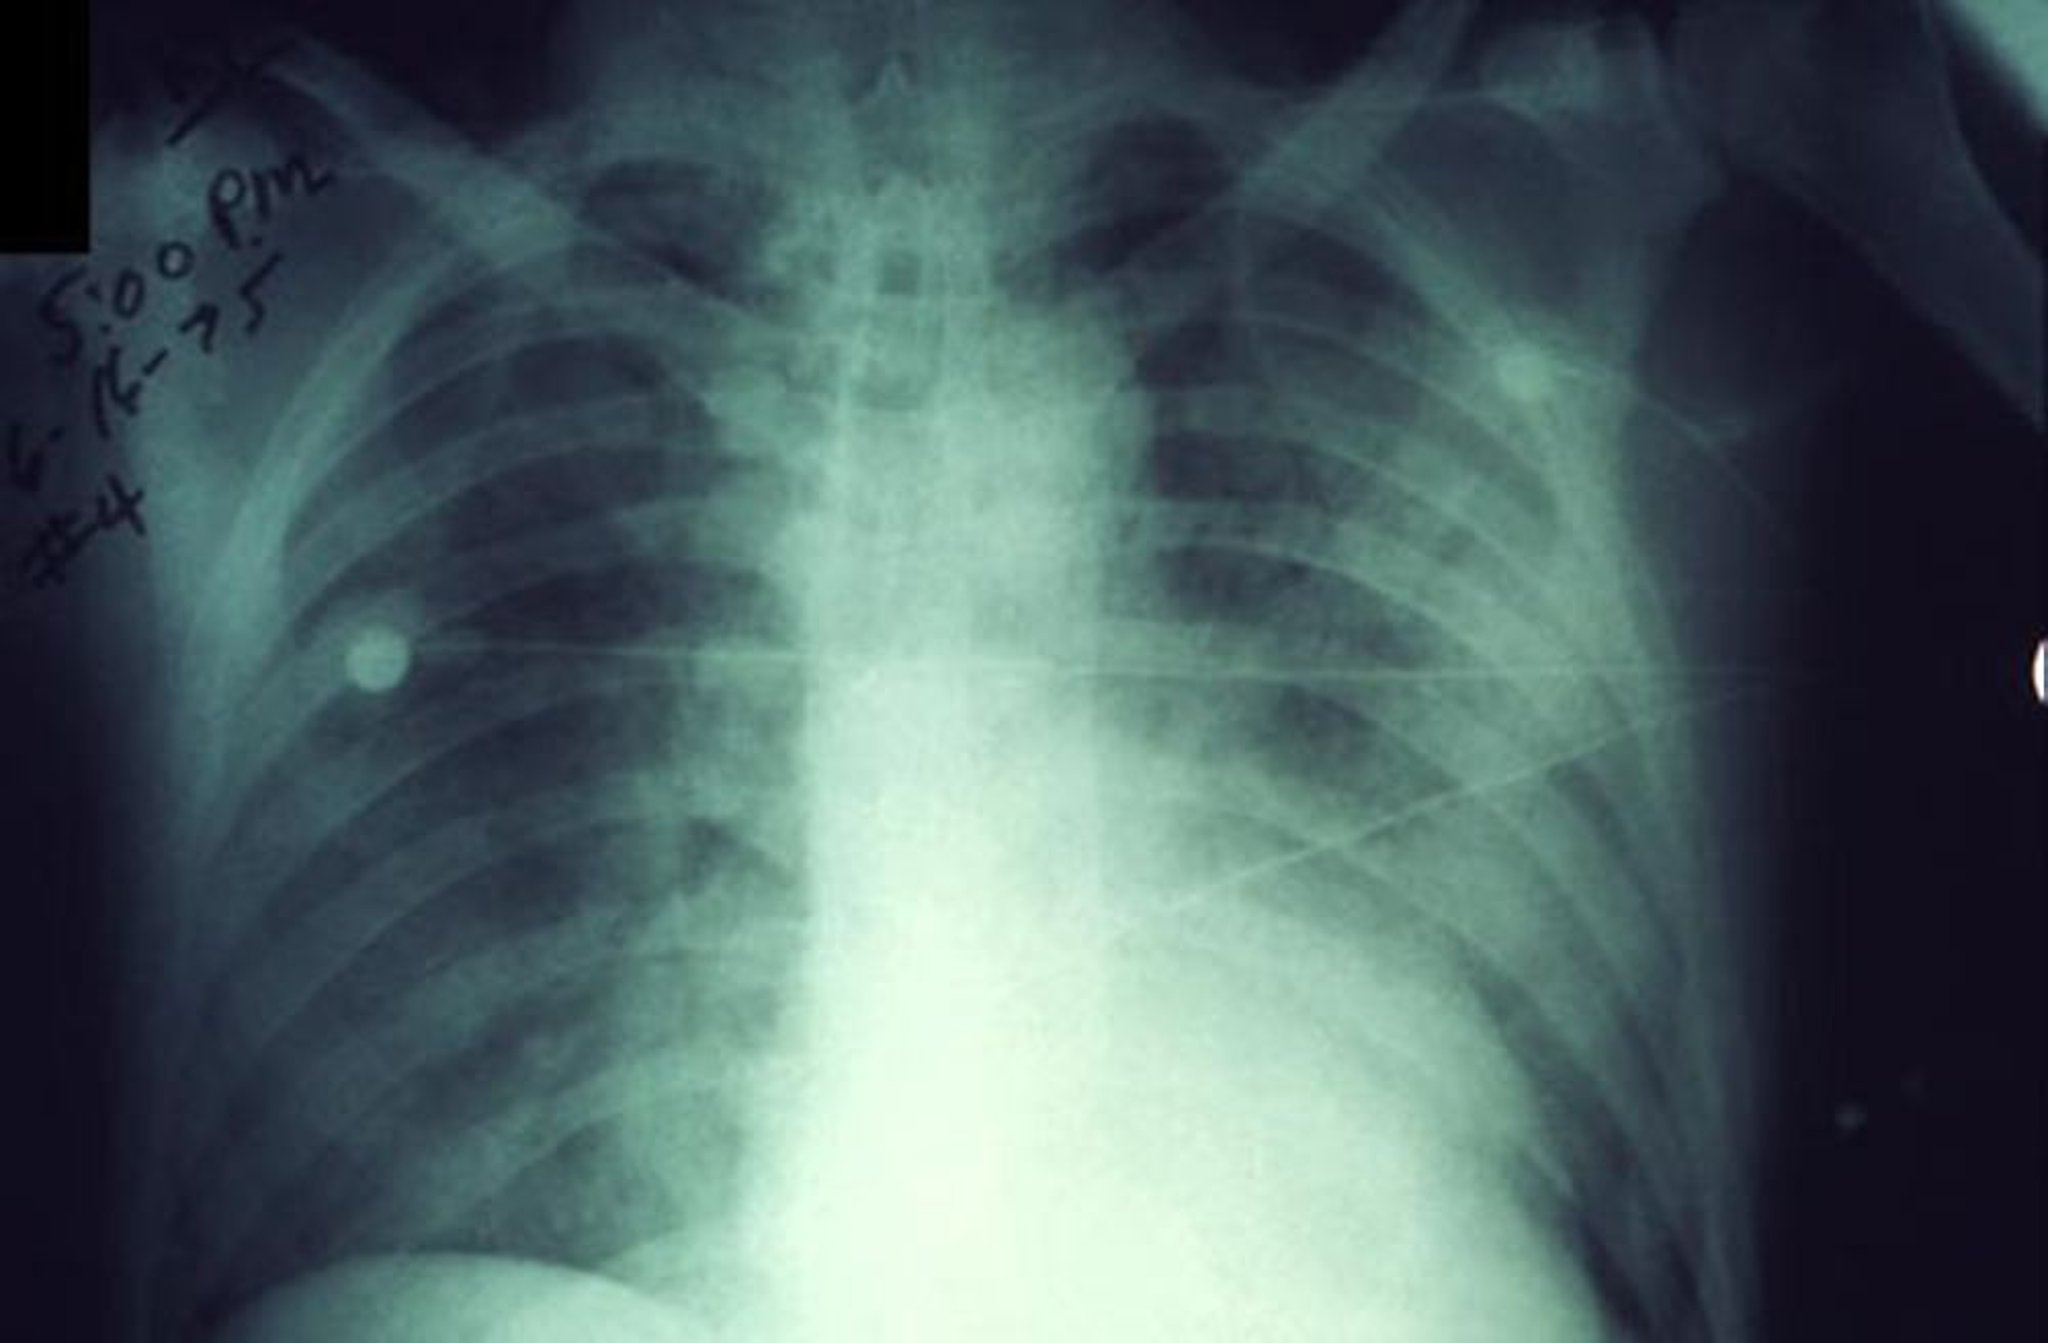

На данном рентгеновском снимке грудной клетки показаны быстро увеличивающиеся инфильтраты при легочной чуме.